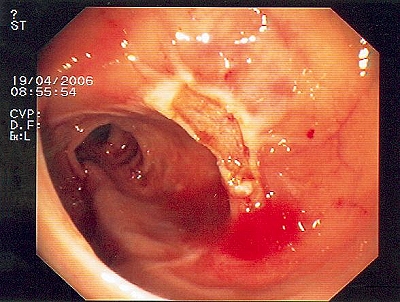

Gut sichtbarer Blutstrahl nach Abtragung eines Polypen

Sichere Blutstillung durch einen Metallclip